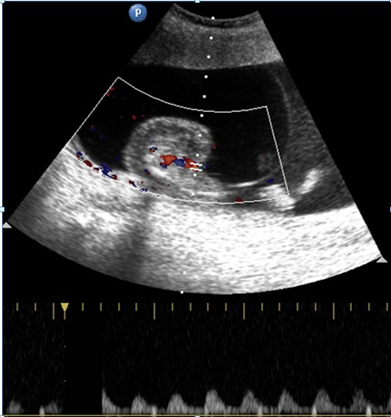

The incidence of the TRAP sequence is estimated as 1% of monozygotic twins, affecting 1/35,000 to 1/50,000 births.1 Most of the cases of TRAP sequence are seen in twins, with only 8% in triplets. The risk increases with multiple pregnancies of higher order.2 Twin reversed arterial perfusion (TRAP sequence) represents a syndrome characterized by partial or complete lack of cardiac development in one of the twins and abnormal vascular communication in the placenta.3 In our case, we had monochorionic triplets with TRAP physiology, which is very rare (Figure 1).

In the TRAP sequence associated with twins, the normal twin ‘pumps’ blood to the abnormal twin, called the ‘recipient’ twin, through abnormal artery-to-artery and venous-to-venous communications in the placenta. This is in conjunction with the vascular anastomosis, which takes place in TRAP syndrome.4 (Figure 2 - Figure 7).

Figure 4,5 Pulsed Doppler of the umbilical artery of the abnormal fetus shows reversal of flow on the spectral waveform.